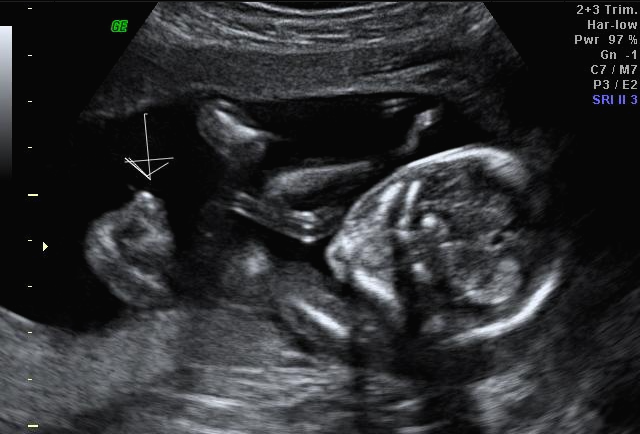

그리고 초음파 봐주시는 분께서 13주차가 되면 정확히 알 수 있으니 다음 주에 오라고 하셔서 일주일 뒤 다시 방문을 했습니다. (위에 사진은 12주 차 때 아들이라고 보여주신 초음파 사진이에요~ 화살표 보면 툭 튀어나와있는 부분을 보여주면서 아들이라고 하셨어요~)

일주만에 더 커있는 우리 트롱이~ 어찌나 꼬물꼬물 귀엽게 움직이던지 ㅎㅎ 트롱이 건강상태를 확인 후 다시 성별을 확인했는데 100프로 아들이라며 지금 병원에서 일을 하시고 경력이 25년 됐다고 믿음을 확실히 주셔서 초음파 검사가 끝나고 바로 부모님께 연락을 드리고 아들 옷 사러 갔어요 ㅋㅋㅋ

아 진짜 전문가는 다르구나~ 이렇게 이른 주수에도 성별을 알 수가 있구나 생각을 했지만 이 시기 때는 성별을 정확히 알 수 없다는 글들을 봐서 살짝~ 의심스럽기도 했지만 그래도 100프로라니깐 ㅎㅎ 믿어보았어요~ 근데 위에 사진을 보면 성별을 알 수 있는 각도 법이 있는데 각도가 딸 같아서 긴가민가~하긴 했지만 의심은 잠시! 전문가 분을 믿기로 ㅋㅋㅋㅋ